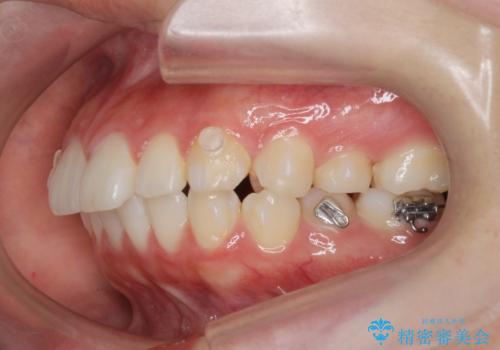

ワイヤー、マウスピースにはそれぞれ得意な動き、不得意な動きがあります。

長所・短所をうまく使い分けることで矯正治療の期間を短縮することができます。